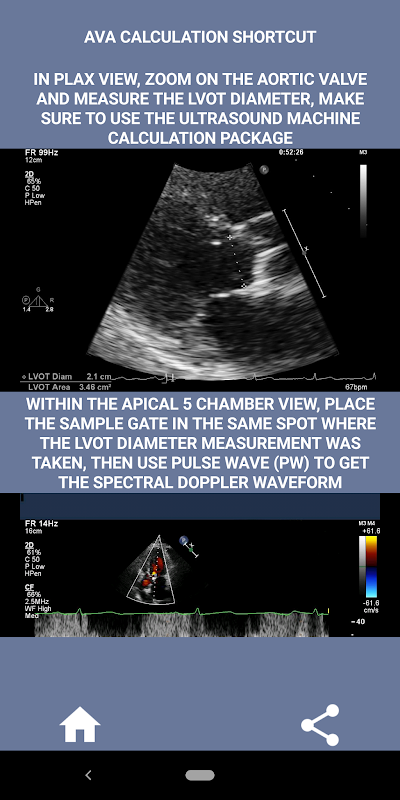

En mi opinión, si un entrevistado puede demostrar firmemente esta habilidad, esa persona tiene una gran ventaja sobre los otros solicitantes que son débiles en esta área (eso es lógico, ya que normalmente hay tantos casos de estenosis aórtica). Si está solicitando un puesto de ecografista cardíaco, alguien que solo necesita actualizar sus habilidades o un estudiante de ecografía, entonces esta aplicación fue diseñada pensando en usted por un ecografista cardíaco en ejercicio. Simple y breve, directo al grano con muchos videos ilustrativos que señalan exactamente dónde medir (por ejemplo, el diámetro del TSVI) y cómo medir según las pautas publicadas de ASE / ICAEL.